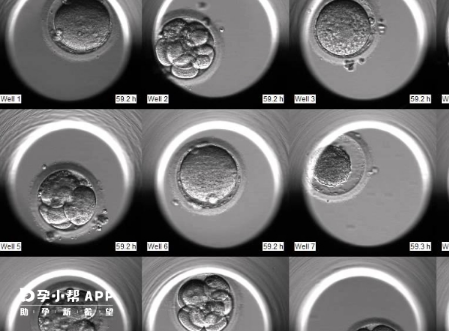

为了满足不同患者的需求,南宁公立医院针对不同情况制定了个性化的治疗方案,从促排卵、取精、胚胎培养到移植等环节都严格遵循科学规范。此外,医院还提供基因检测等辅助诊断服务,帮助提高试管婴儿成功率。

试管婴儿移植过程通常分为以下几个步骤: